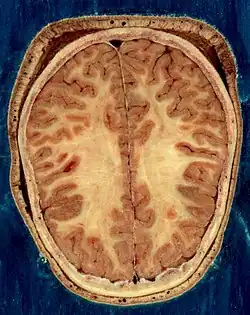

Строение головного мозга

Объём мозга большинства людей находится в пределах 1250—1600 кубических сантиметров и составляет 91—95 % ёмкости черепа. В головном мозге различают пять отделов: продолговатый мозг; задний, включающий в себя мост, мозжечок и эпифиз; средний; промежуточный; и передний мозг, представленный большими полушариями. Наряду с приведённым выше делением на отделы, весь мозг разделяют на три большие части:

Кора большого мозга покрывает два полушария головного мозга: правое и левое.

Оболочки головного мозга

Головной мозг, как и спинной, покрыт тремя оболочками: мягкой, паутинной и твёрдой.

Мягкая, или сосудистая, оболочка головного мозга (лат. pia mater encephali) непосредственно прилегает к веществу мозга, заходит во все борозды, покрывает все извилины. Состоит она из рыхлой соединительной ткани, в которой разветвляются многочисленные сосуды, питающие мозг. От сосудистой оболочки отходят тонкие отростки соединительной ткани, которые углубляются в массу мозга.

Паутинная оболочка головного мозга (лат. arachnoidea encephali) — тонкая, полупрозрачная, не имеет сосудов. Она плотно прилегает к извилинам мозга, но не заходит в борозды, вследствие чего между сосудистой и паутинной оболочками образуются подпаутинные цистерны, наполненные спинномозговой жидкостью, за счёт которой и происходит питание паутинной оболочки. Самая большая, мозжечково-продолговатая цистерна, размещена сзади четвёртого желудочка, в неё открывается срединное отверстие четвёртого желудочка; цистерна боковой ямки лежит в боковой борозде большого мозга; межножковая — между ножками мозга; цистерна перекресток — в месте зрительной хиазмы (перекресток).

Твёрдая оболочка головного мозга (лат. dura mater encephali) — это надкостницы для внутренней мозговой поверхности костей черепа. В этой оболочке наблюдается наивысшая концентрация болевых рецепторов в организме человека, в то время как в самом мозге болевые рецепторы отсутствуют (см. Головная боль).

Твёрдая мозговая оболочка построена из плотной соединительной ткани, выстланной изнутри плоскими увлажнёнными клетками, плотно срастается с костями черепа в области его внутренней основы. Между твёрдой и паутинной оболочками находится субдуральное пространство, заполненное серозной жидкостью.